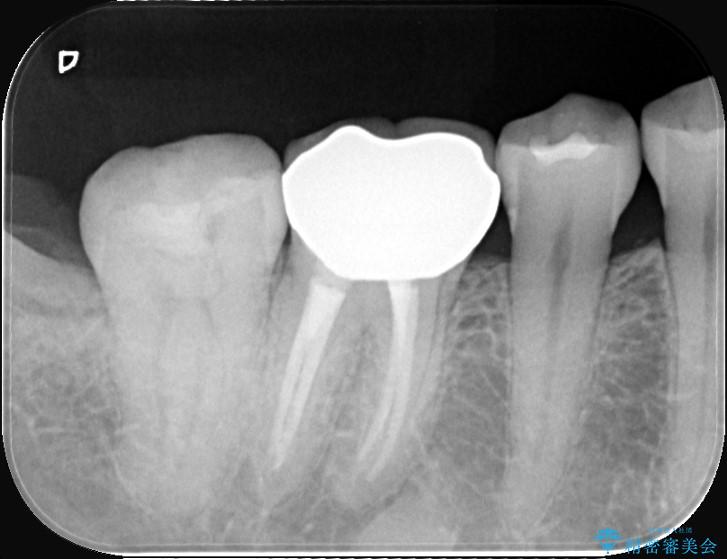

診査の結果、右下7番目の歯の奥側の面や手前の歯との間にう蝕があり、噛む面にも蝕処置によるレジン材料が詰まっていました。

う蝕、古い材料を全て除去し、セラミックインレーでやり替えることとしました。

右下奥歯の広範囲な虫歯と劣化した古い詰め物をすべて除去し、新しくセラミックインレーで修復しました。装着時にはラバーダムを使用し、湿気を遮断した状態で精密に接着させています。